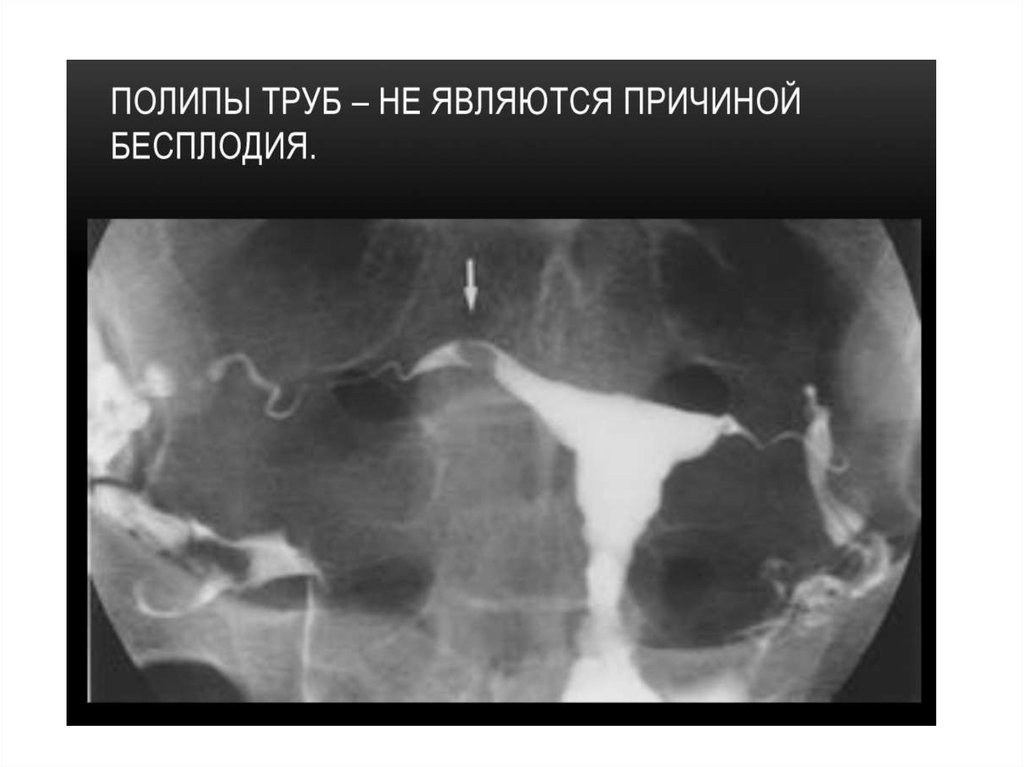

• Гистеросальпингографией (ГСГ) называют

метод рентгенодиагностики состояния

фаллопиевых труб и внутренней полости

матки, их проходимости и строения при

помощи введения контрастного вещества в

полость матки и труб